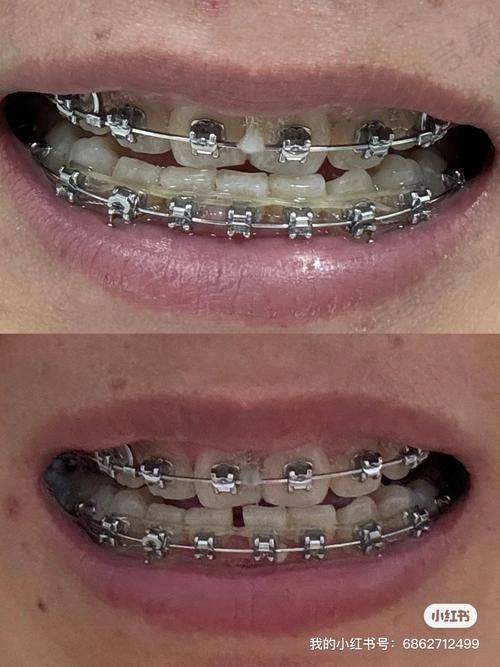

烟台莱山德韩口腔门诊部成立于2022年6月20日,公司规模为100 - 499人。门诊部设有多个专精科室,涵盖了口腔种植、口腔正畸、口腔修复、口腔综合治疗等多个领域。其中,数字化种植中 心和美颜正畸中 心是其特色科室。数字化种植中 心配备了德国卡瓦口腔CT、3D导板打印系统等精良设备,实现了“数字化种植”,能够为患者提供精细、效率高的种植方案。美颜正畸中 心引入了美国隐适美iTero口扫仪,5分钟即可生成牙齿3D模型,并动态演示矫正全过程,为患者提供个性化的正畸方案。此外,门诊部还注重服务质量和患者体验,为患者提供全方面的口腔医疗服务。

烟台莱山德韩口腔门诊部拥有多个特色项目,具有显著的独特之处和优势。在数字化种植中 心,配备德国卡瓦口腔CT、3D导板打印系统,实现“数字化种植”。ALL - ON - 4半口种植仅需4颗植体半口牙,支持即刻负重,术后24小时戴临时冠;百康特种植套餐1280元起(含植体 + 基台 + 牙冠),瑞士诺贝尔高端植体可选,能有效避开神经,全程几乎微痛。美颜正畸中 心引入美国隐适美iTero口扫仪,5分钟生成牙齿3D模型,并动态演示矫正全过程。金属自锁托槽矫正周期缩短30%,儿童配合度更高;隐形矫正双膜技术(时代天使/隐适美),薄厚膜交替佩戴加速牙齿移动;价格透明,金属托槽4980元起,全隐形矫正8888元起(2025年活动价)。此外,门诊部还设有独立诊室,搭配空气系统,保护隐私的同时降低交叉感染风险;器械消毒采用“六步灭菌法”,实现“一人一机一用”。

烟台莱山德韩口腔门诊部在2025年2月推出了一系列优惠活动,价格具有较强的竞争力。在种植牙方面,韩国登腾种植牙含基台 + 全瓷冠,活动价低至1280元/颗起,同城质保10年;美国皓圣种植牙即拔即种当天用牙,3980元/颗起,骨结合速度提升40%。牙齿矫正项目中,金属托槽矫正传统方案活动价4980元起,学生专享;时代天使冠军版隐形矫正智能方案19800元起,矫正周期缩短30%。补牙项目里,普通树脂补牙120 - 260元,采用3M Z350XT纳米树脂,比医院便宜30%。根管治疗方面,前牙根管治疗600 - 900元,使用德国VDW机用镍钛锉,比私立诊所便宜25%。活动假牙中,传统树脂活动假牙经济实用型999元起。门诊部收费便宜的原因主要有供应链优势、技术降本增效、客群定位和增值服务盈利等。例如,植体/托槽集采,韩国登腾植体采购价较单体诊所低52%;数字化种植导板减少手术时间50%,使医生日均接诊量翻倍。